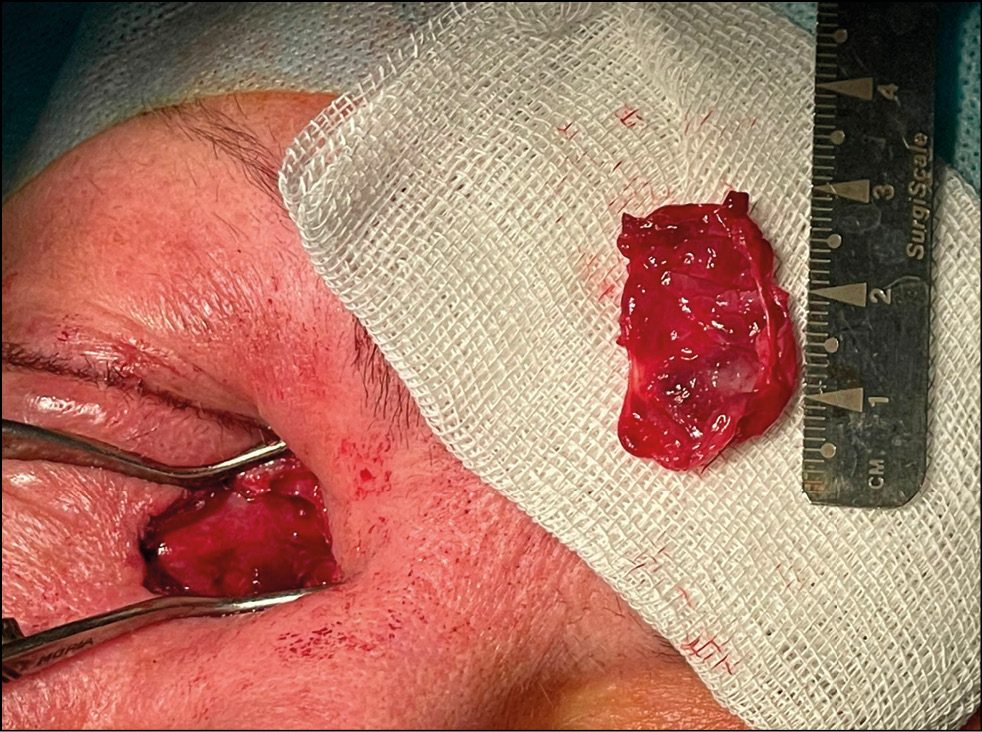

Пациентке было показано хирургическое лечение под общим наркозом. Проведена на правом глазу дакриоцистэктомия радиоволновая. Осуществлён разрез кожи длиной 15 мм в проекции слёзного мешка. Разделены глубокие ткани и рубцы тупым и острым путём, выполнен гемостаз. Слёзный мешок выделен, он имел очень большие размеры с растяжением и смещением в орбиту и в сторону щеки со смещением глазного яблока кнаружи и кверху. Произведено выделение и удаление слёзного мешка радиоволновым ножом с коагуляцией места выхода в слёзно-носовой канал и входа канальцев в слёзный мешок. В процессе хирургического вмешательства из слёзного мешка было удалено 6,5 мл жидкого содержимого в виде прозрачной опалесцирующей жидкости. Гнойного отделяемого отмечено не было. Рана промыта растворами антисептиков и антибиотиков. В рану засыпан сухой антибиотик. Рана ушита послойно: мягкие ткани, кожа. На кожу наложены узловые швы викрилом 6/0. Проведена обработка 0,3% глазной мазью «Флоксал», наложена бинтовая повязка. Удалённый увеличенный и деформированный слёзный мешок направлен на гистологическое исследование (рис. 3).

Рис. 3. Удалённый слёзный мешок.